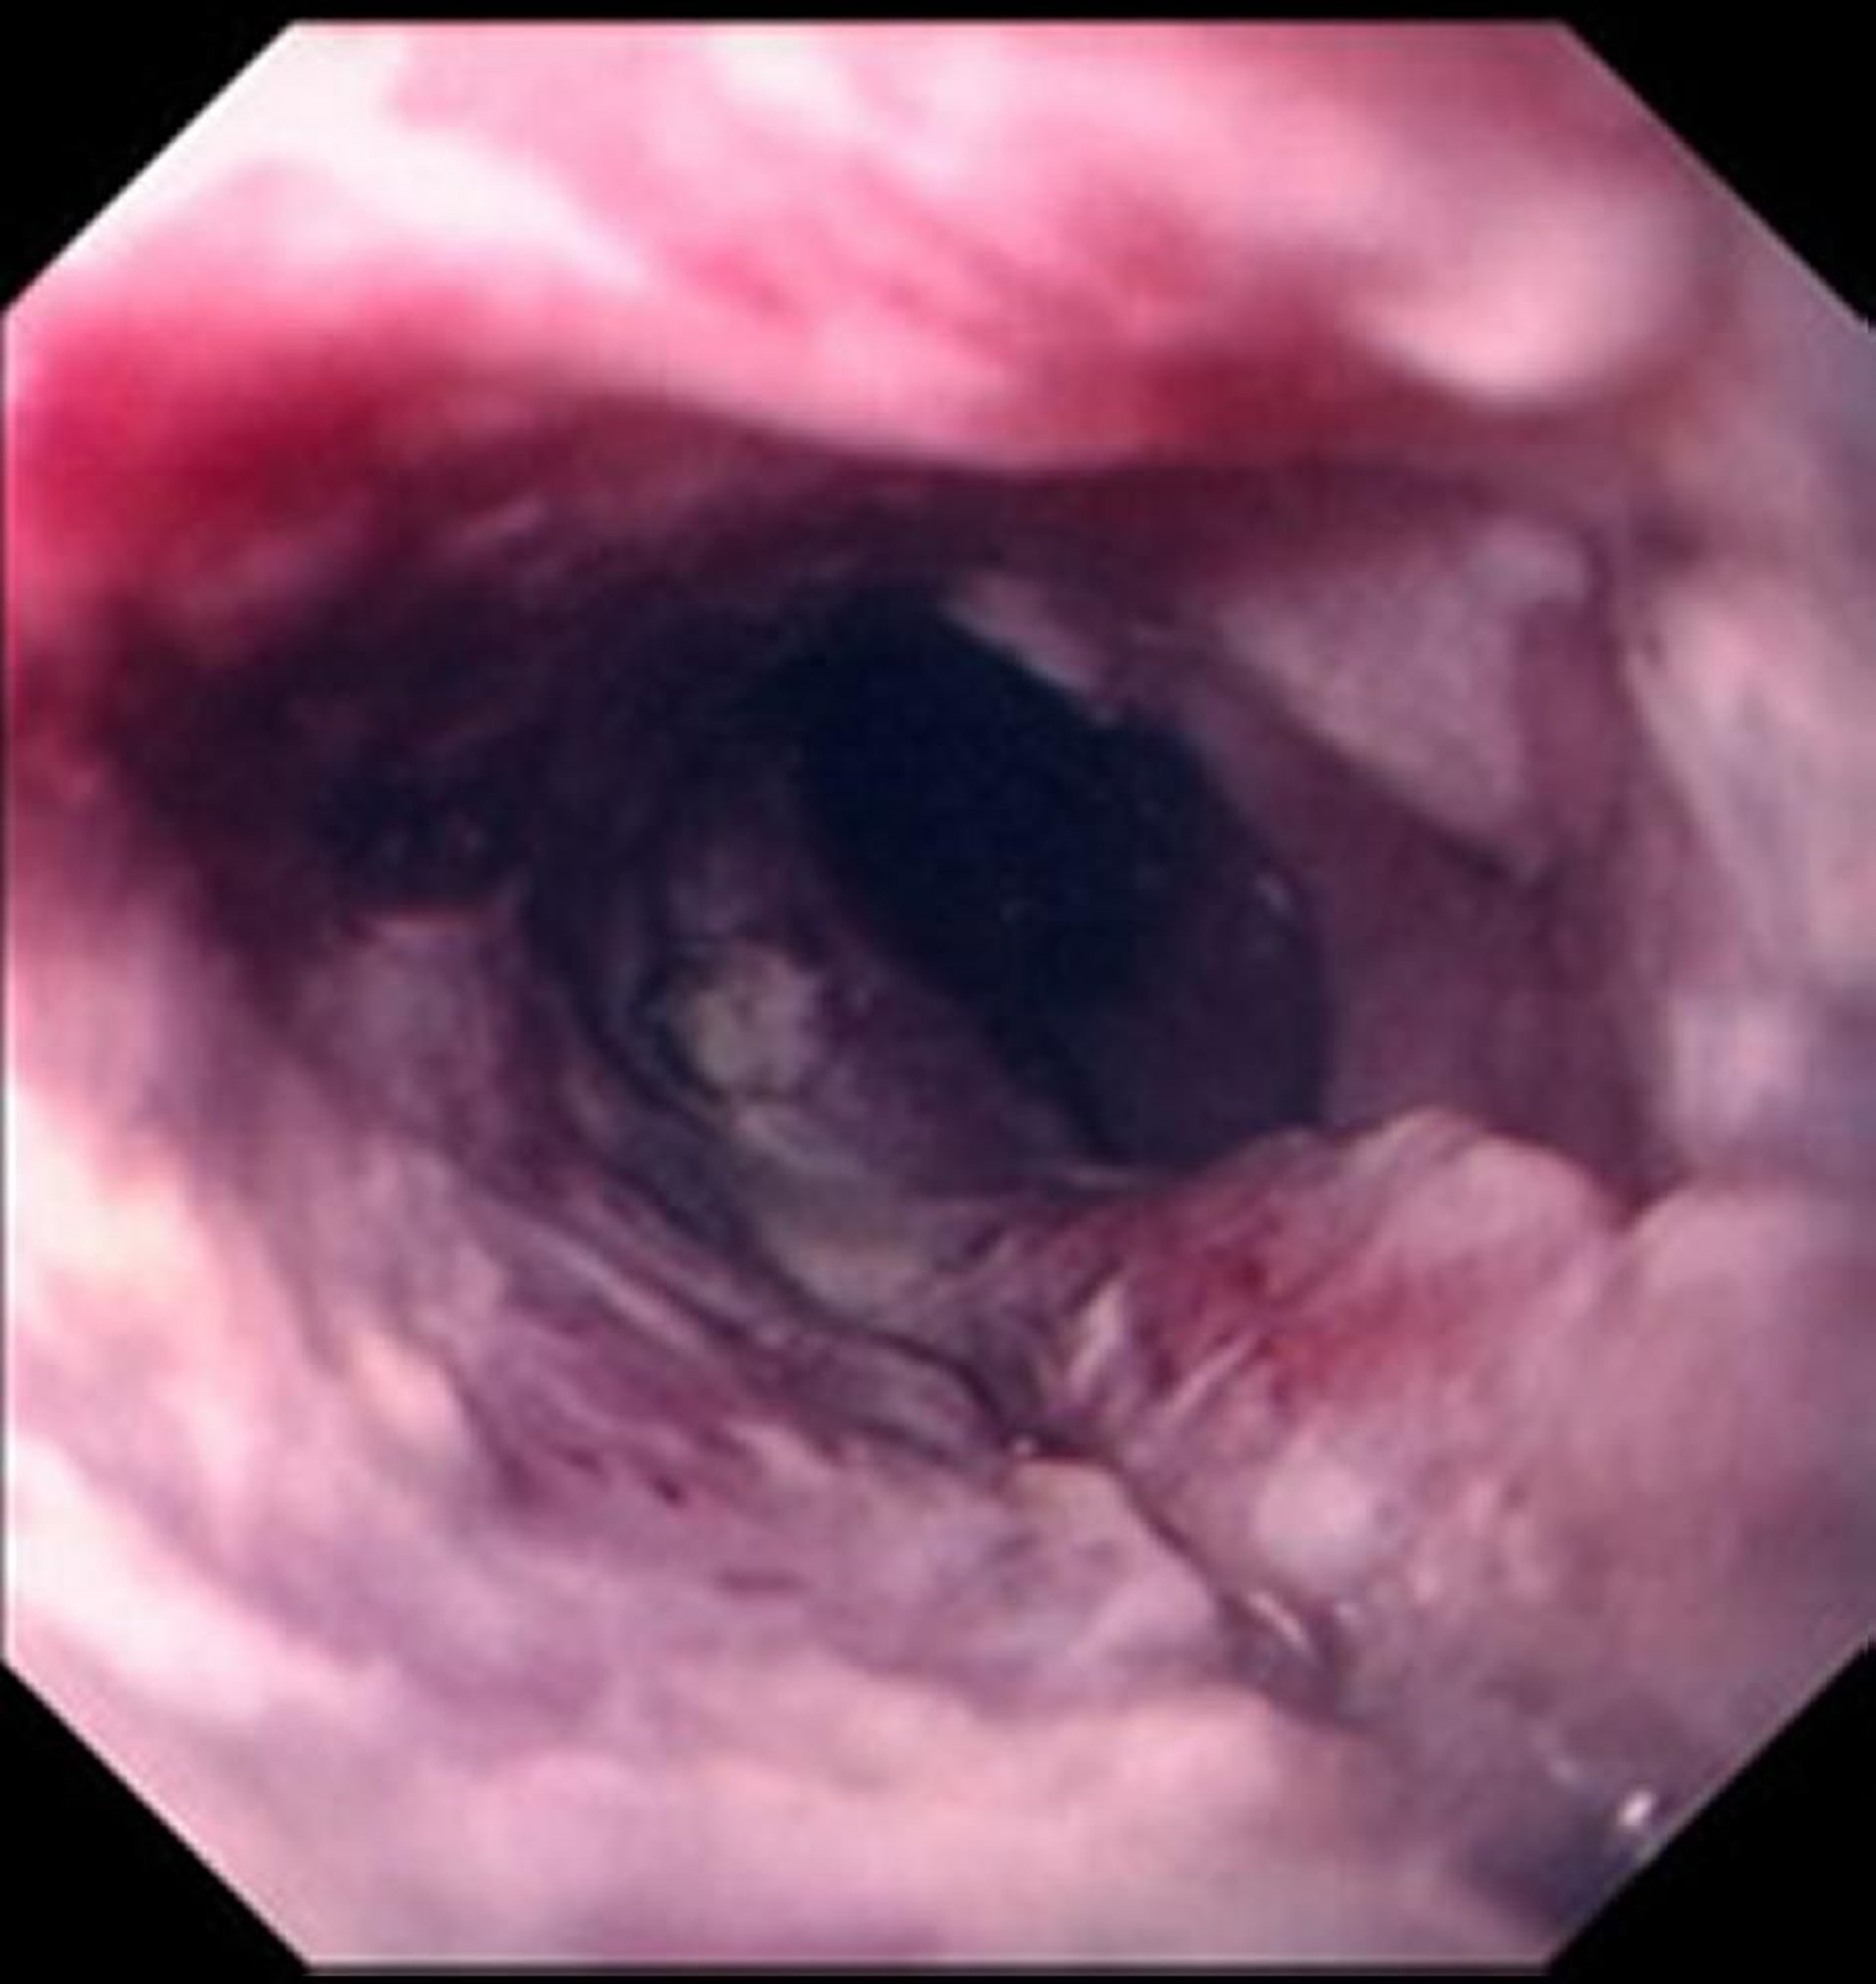

Плоскоклеточный рак пищевода

Плоскоклеточный рак, как правило, проявляется в виде изъязвленного, рваного образования, перекрывающего просвет пищевода.

Images provided by David M. Martin, MD.